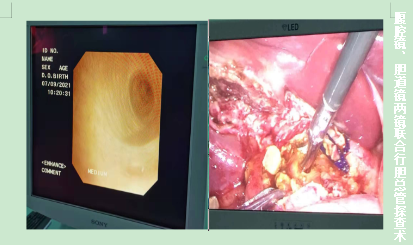

近25年肝胆外科成为其它亚专科发展的基石,开展了腹腔镜胆囊切除术、门脉高压门奇断流术、胰十二指肠切除术、两镜联合胆总管切开取石术、腹腔镜脾切除术、肝部分切除术、精准肝叶切除术等复杂手术,其中两镜联合治疗胆总管结石在孝感市县级医院处于领先地位。